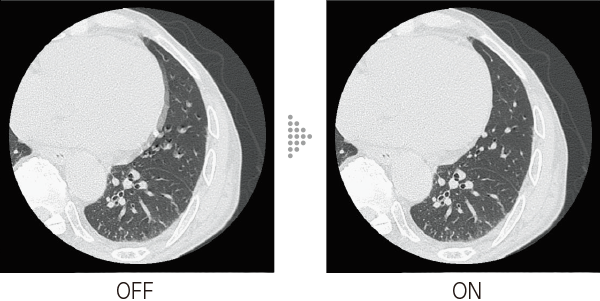

Intelli IPV is an image reconstruction technique developed with AI technology*3. Reconstruction processing has been speeded up by using images obtained through sufficient iterative processing as training data. Based on the Fujifilm's Visual Model, reconstruction processing using RawData brings the NPS(Noise Power Spectrum)closer to FBP(Filtered Back Projection)and keeps the image texture, even at a high noise reduction rate. It reduces image noise by up to 90%*4 and radiation exposure by up to 83%.*5 It also improves low contrast detectability by up to 2 times.*5

- *4 Compared to FBP. It was measured using Intelli IPV intensity level Strong5 and tested to a water phantom. Depending on the clinical task, patient size, anatomic location, and clinical examination, the effect obtained may be smaller.

- *5 Compared to FBP. It was measured at 0.625 mm slice thickness using Intelli IPV intensity level Strong5 and tested to MITA CT IQ phantom CCT189, Phantom Laboratory using the model observer method results. Depending on the clinical task, patient size, anatomic location, and clinical examination, the effect obtained may be smaller.